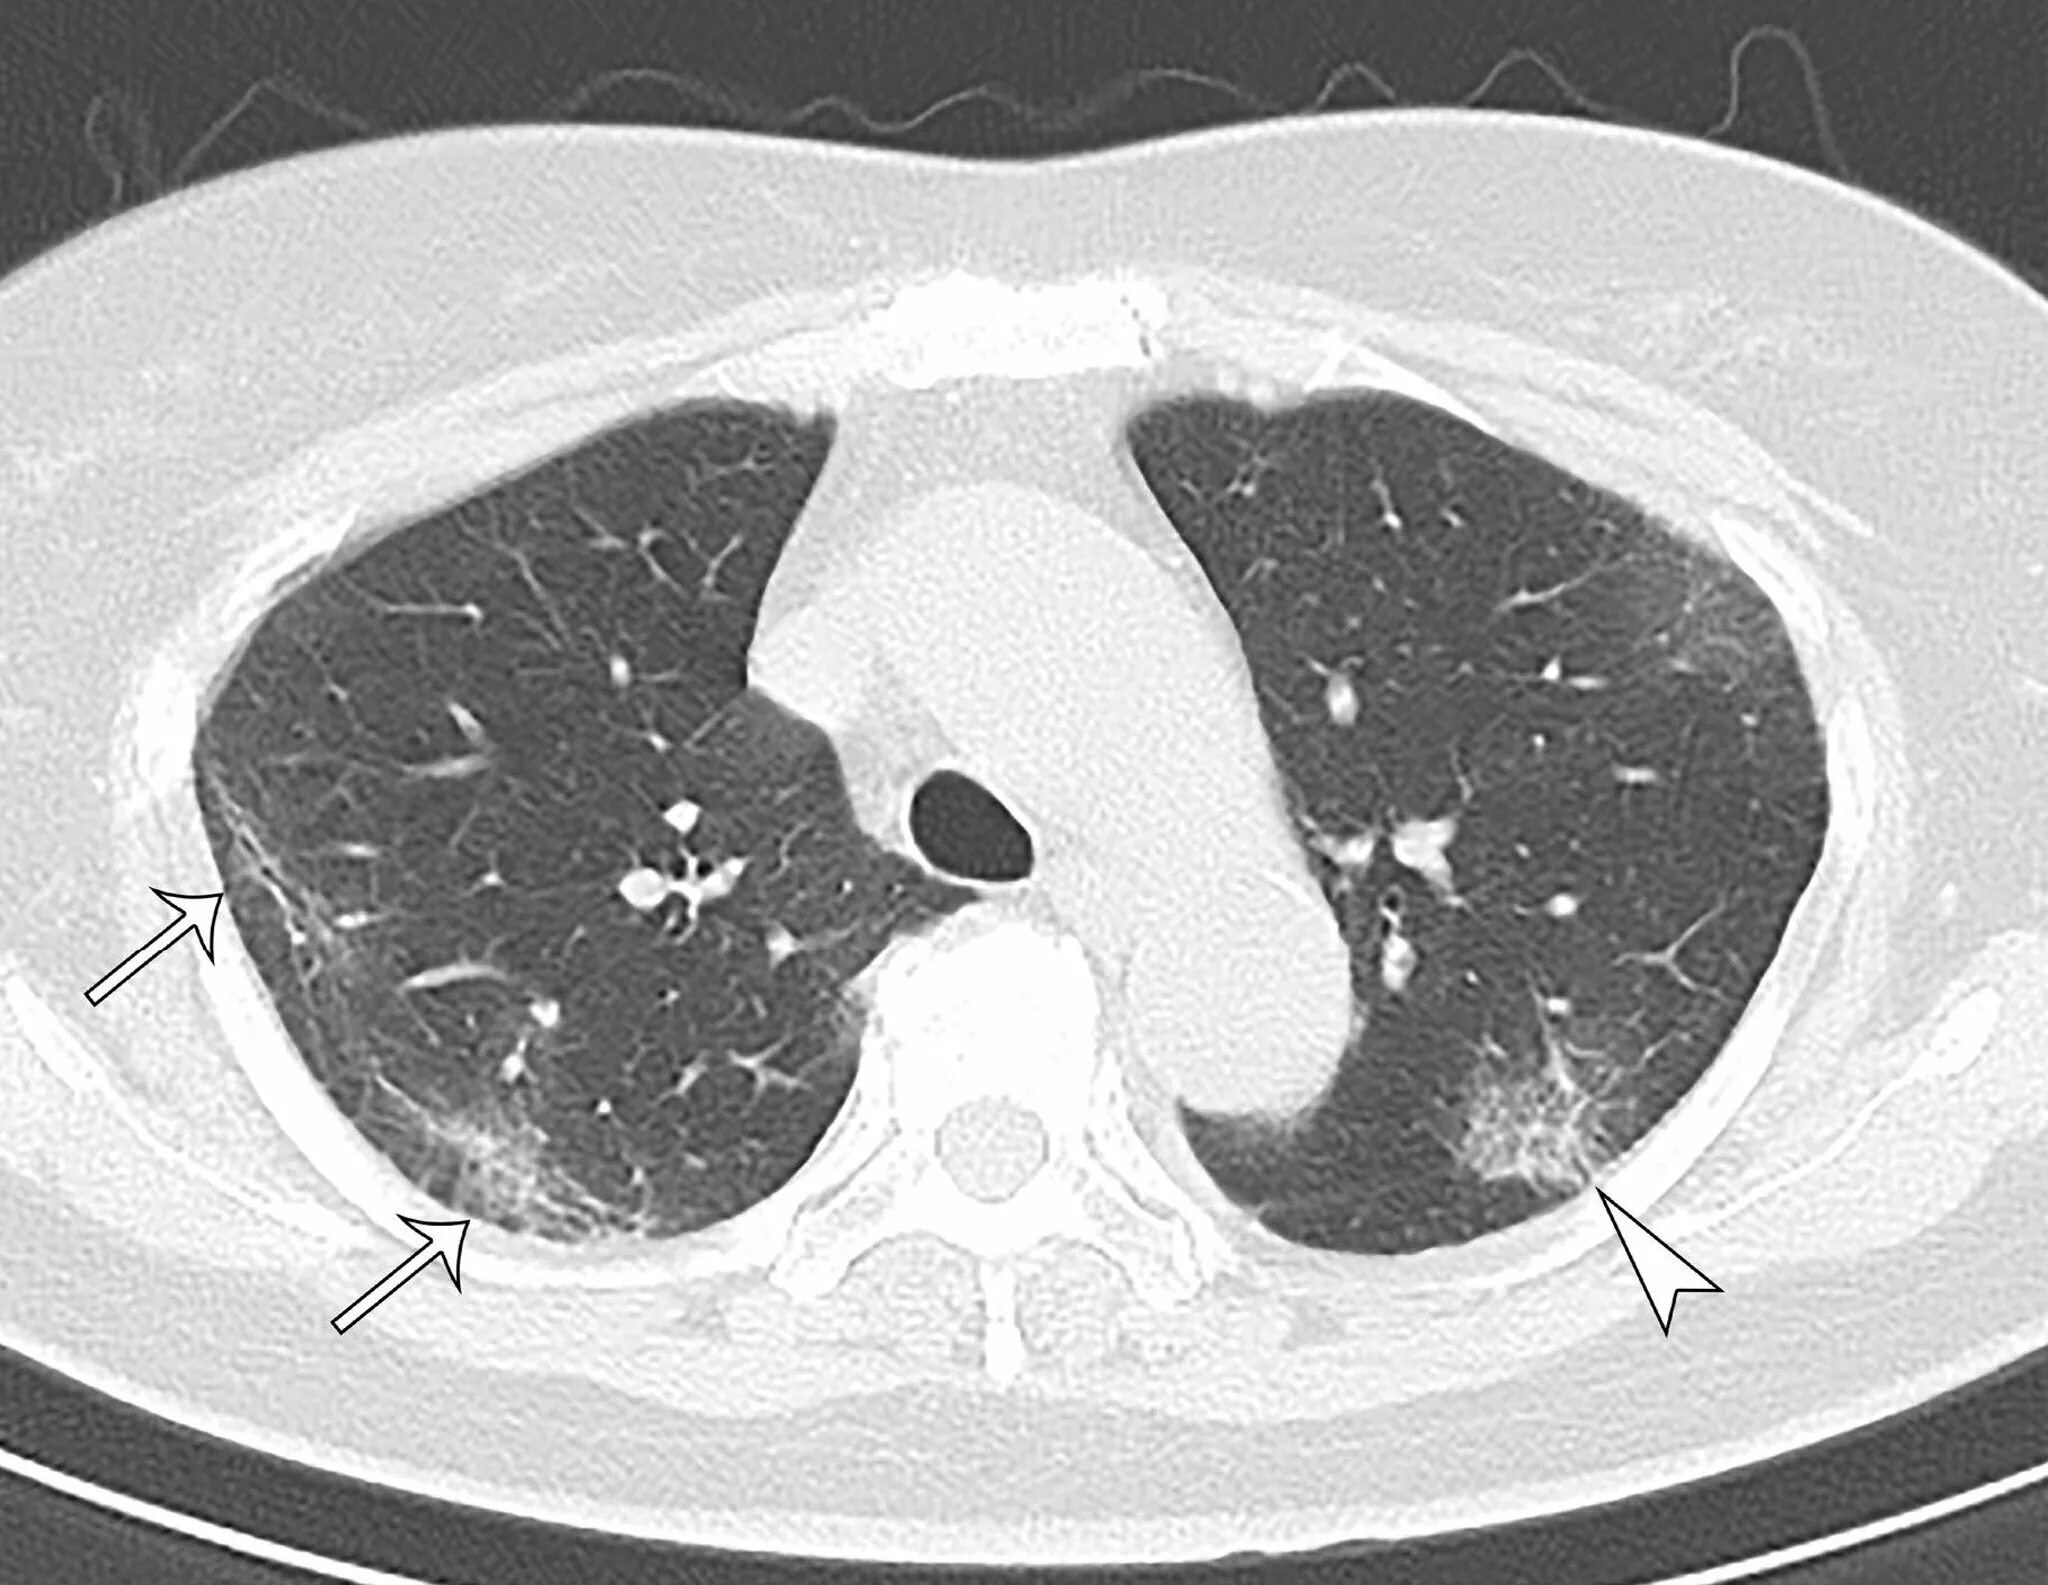

Кт после ковид